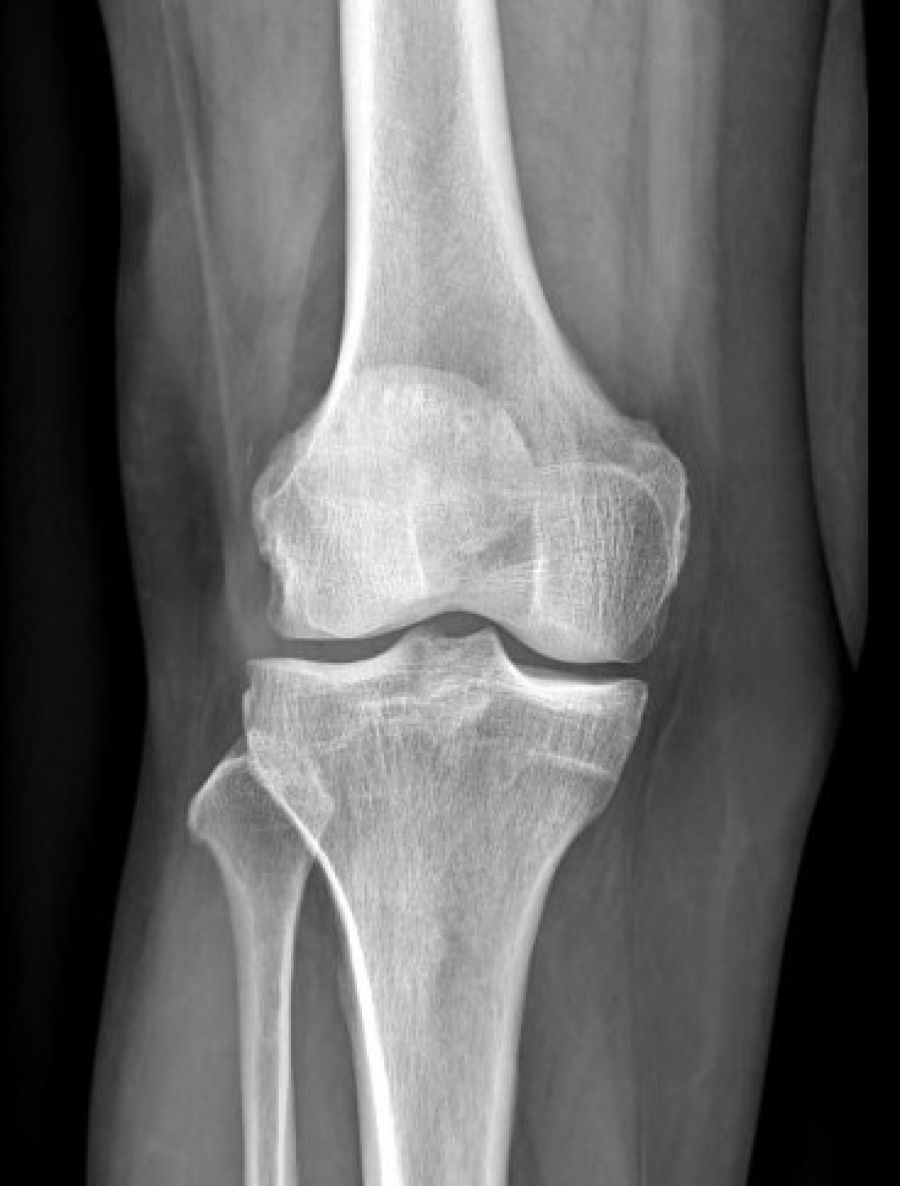

Les radiographies sont fréquemment requises entre autres, pour la recherche d'une fracture dans le cadre d'un traumatisme, les bilans d'arthrose, les bilans statiques, l'étude des poumons au cours d'une radiographie thoracique ...